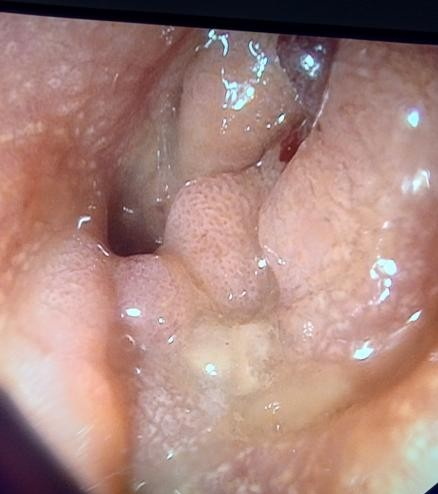

Colonic stent placement was performed under general anesthesia. The patient was placed in the left lateral decubitus position and a double channel therapeutic gastroscope (Olympus America) was passed into the rectum until an area of complete colonic obstruction was reached in the sigmoid colon. The fluoroscopy was also used in this procedure. The luminal obstruction was so severe we have to use ERCP cannula and 0.025 in angled visiglide wire (Olympus America) under fluoroscopy to access the obstructed proximal part of the dilated colon through the tumor. Then a 25 mm x 90 mm Boston Scientific colonic stent was deployed (Figure5) successfully, and stool was visualized coming through the stent from the obstructed part of the colon (Figure 6). A follow-up x-ray of the abdomen was used to confirm there was no adverse event like perforation (free air under the diaphragm).

Figure 6. Stent placement and deployment.

Figure 6